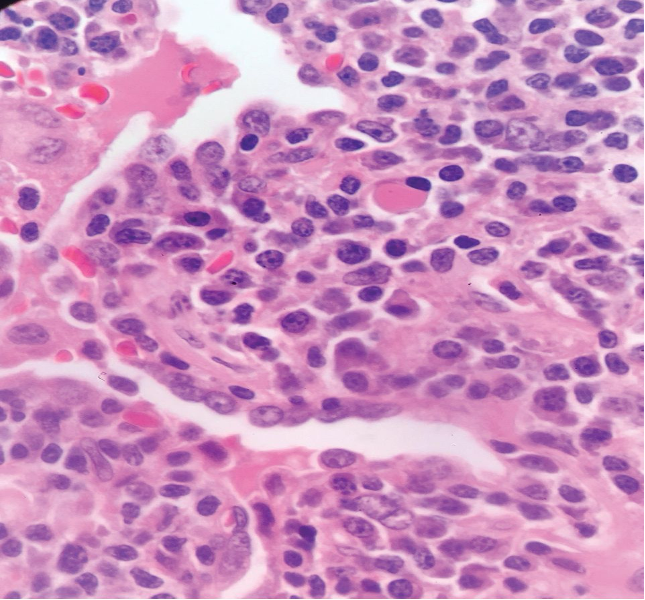

Section H and E x400. Mass in the wall of the small intestine in a 72 year old male patient who presented with frequent diarrhoea. Make you diagnosis.

Maltoma – small intestine- monocytoid B cells many showing plasmacytoid differentiation.